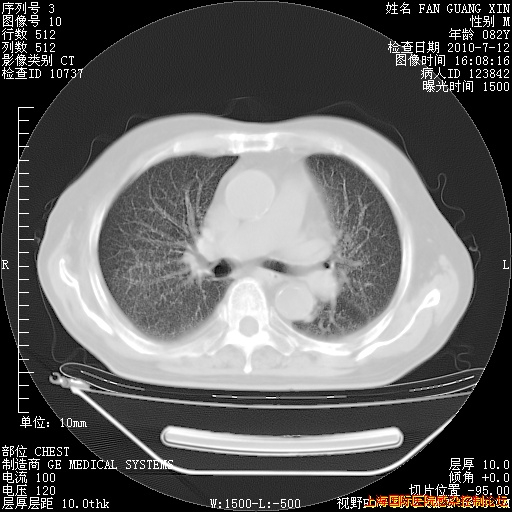

今天CT

整整相隔30天的肺部CT好像有所好转啊。甲强龙减量第3天,需要观察体温。

海管,自昨日你和我通完话后,不知您岳父消化道症状有无缓解?体温怎样?阅读7.12日胸部ct,个人认为目前激素治疗是有效的,甲强龙减量是适宜的。因在抗痨治疗,需密切观察肝功、肾功能和血常规。不过,老年、长期住院和大量使用激素,很担心菌群失调发生